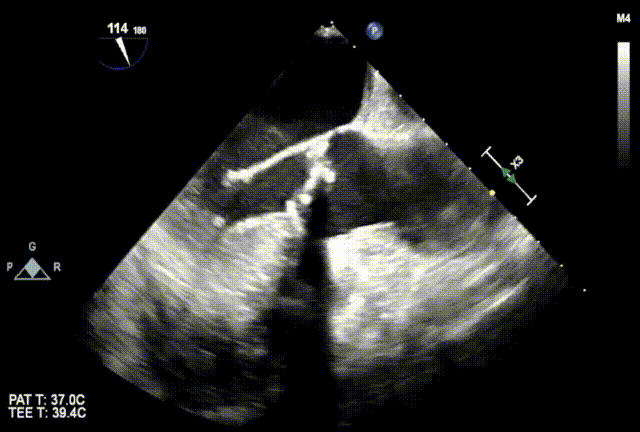

超声评估

后扩否?

瓣膜是否有弹出风险?如何避免?

再次与根部造影对比

通过与术前主动脉根部造影的对比,确认两侧深度平均但较临界,可谨慎操作下尝试球囊后扩张以使流入端瓣架充分膨胀贴合自体瓣环,减少瓣周漏。

最终结果